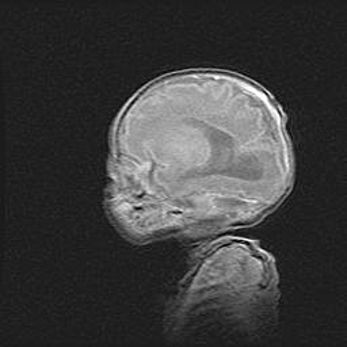

Неполная лизэнцефалия (пахигирия). Открытая гидроцефалия.

Возраст: 17 дней

Вес: 3110 г

Пол: мужской

Окружность головы: 33,5 см

Срок гестации: 35-36 недель

Лизэнцефалия—недоразвитие корковой пластинки и мозговых извилин в результате нарушения миграции нейронов коры. Поверхность мозговых полушарий гладкая. Микроскопически выявляется отсутствие нормальных слоев коры и скопление групп нейронов в подкорковом белом веществе.

Пахигирия—уменьшение числа вторичных извилин. В пораженном полушарии нервные клетки образуют толстый недифференцированный слой с неправильно расположенными нервными волокнами и группами гетеротопных клеток. Нервные клетки незрелые. Белое вещество истончено. При этом нередко аномально развит корково-спинномозговой путь.